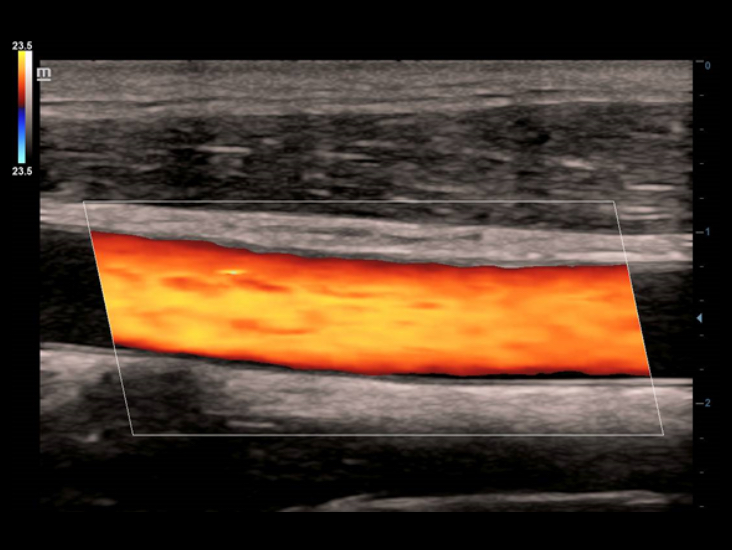

Trasduttori ComboWave

ComboWave utilizzano un nuovo tipo di materiale piezoelettrico composito per ottimizzare efficacemente lo spettro acustico e ridurre l'impedenza acustica. Se integrati con la tecnologia 3T, distintiva di Mindray, i trasduttori lineari ComboWave garantiscono prestazioni eccezionali con risoluzione dâimmagine e uniformitĂ eccezionali nelle applicazioni relative a tiroide, seno, vascolari e altro ancora.

Smart Track

Con un semplice tocco, Smart Track consente di ottenere una visualizzazione ottimizzata rapida e intelligente dell'imaging vascolare. ? in grado di ottimizzare lo spettro del colore, del power e del PW mediante il funzione di tracking automatico e ridurre i passaggi che richiedono molto tempo, semplificando cosĂŹ il flusso di lavoro per gli esami vascolari.